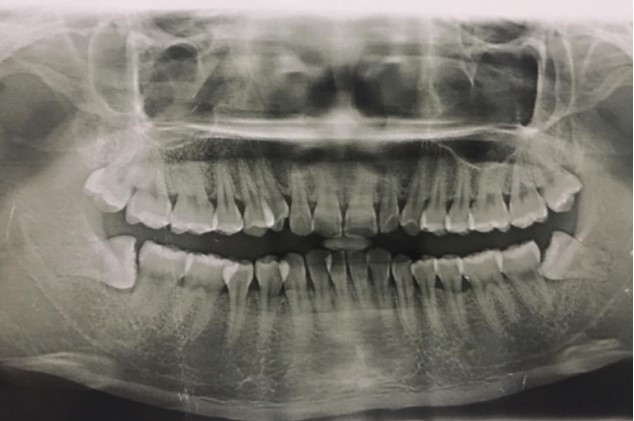

患者,男,38歲。上前牙變色1年,自述上前牙5年前受過外傷,唇側(cè)傾斜,檢查可見左上1牙冠變色,牙冠缺損近1/2,牙髓測試無反應(yīng),X線根尖片顯示患牙無明顯異常,全景片顯示雙側(cè)下頜智齒近中阻生,之前有發(fā)炎化膿病史,目前無咀嚼不適??谇黄溆酂o異常。

檢查情況及X線片見下圖: